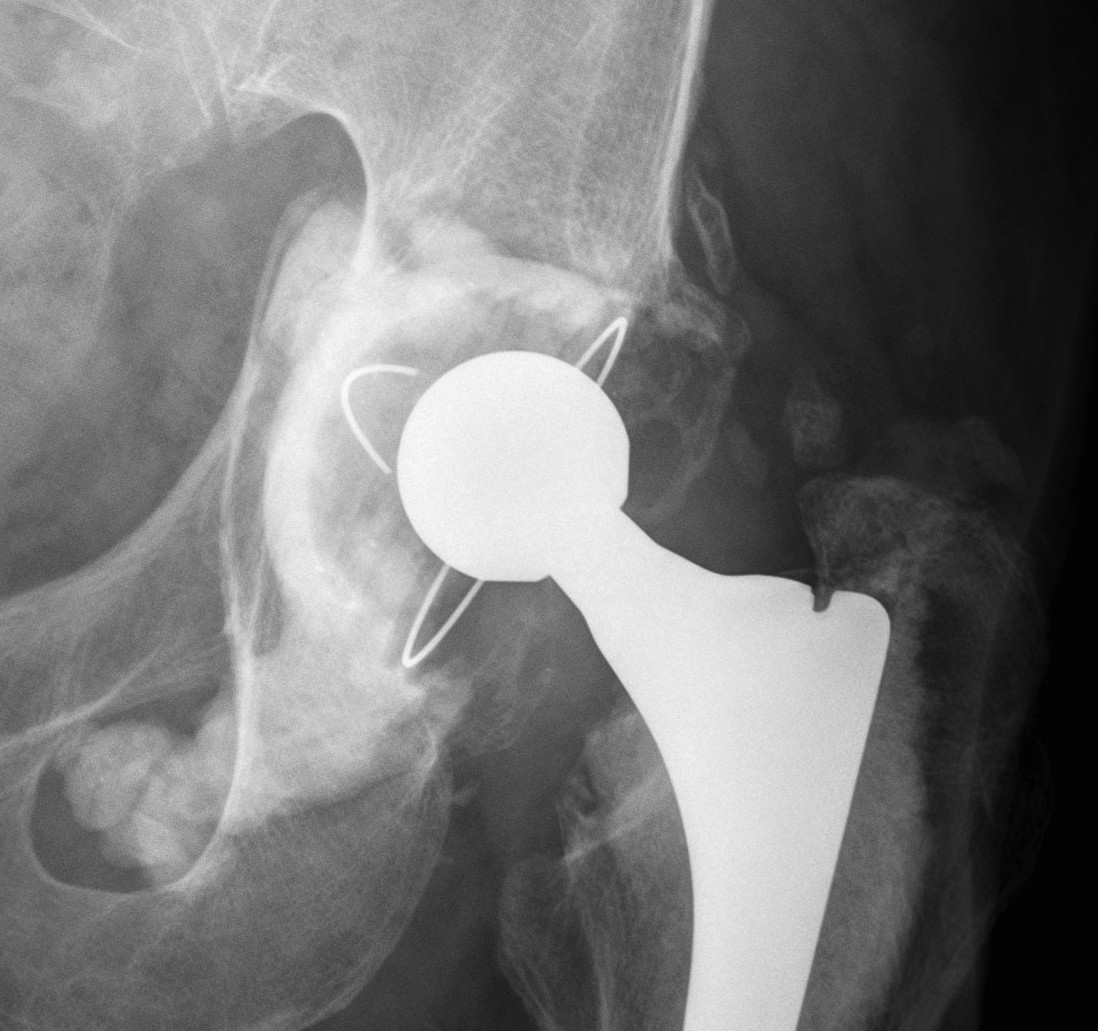

3. Cup Cage Reconstruction

Technique

- large tantalam cup inserted for reconstitution of discontinuity

- bone graft inserted

- cage, cement in cup